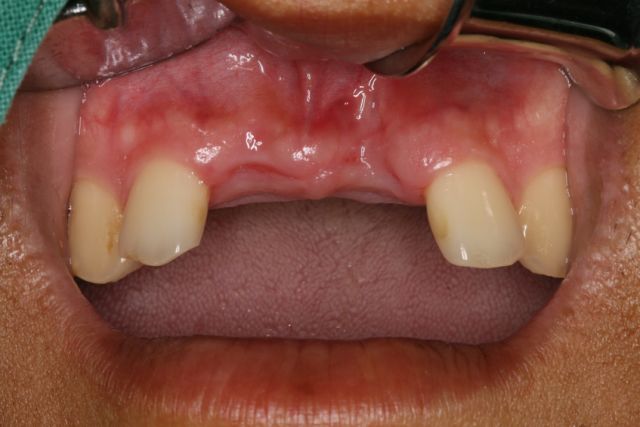

4.軟組織修復(fù)型材料在附著齦增厚術(shù)的應(yīng)用

軟組織修復(fù)型附著齦增厚術(shù)的應(yīng)用

?

牙周治療、拔牙后唇側(cè)

鄂側(cè)